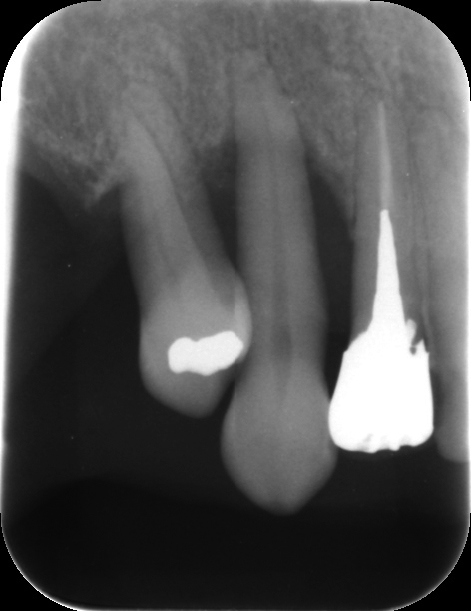

歯周病が進行すると、歯を支える骨が溶けて減少していきます。外から見えない骨の状態を評価するためには、X線検査を行います。当院では、X線検査に「CT」を使用しています。一般的には「レントゲン」と呼ばれるX線検査が知られていますが、二次元の画像を取得するレントゲンに比べて、CTはお口の周囲からの立体的かつ鮮明な映像を撮影することができます。

歯周病が重度に進行すると、歯を支える骨が溶けて歯がぐらついてきます。この状態のままだと自然と歯が抜けてしまうことから抜歯を選択する歯科医院もあります。しかし、抜歯せずとも骨が再生し歯が安定すれば歯が抜けてしまうことはありません。

当院では、歯を支える骨を再生させる「歯周組織再生療法」という治療法で、抜歯機会を減らす取り組みを行っています。

歯肉を外科的に切開し、骨が失われた部分に「エムドゲイン」や「リグロス」といった、骨を再生させる特殊なたんぱく質を含む薬剤を塗布します。個人差はありますが、骨の再生にはおよそ数ヶ月から1年程度かかります。